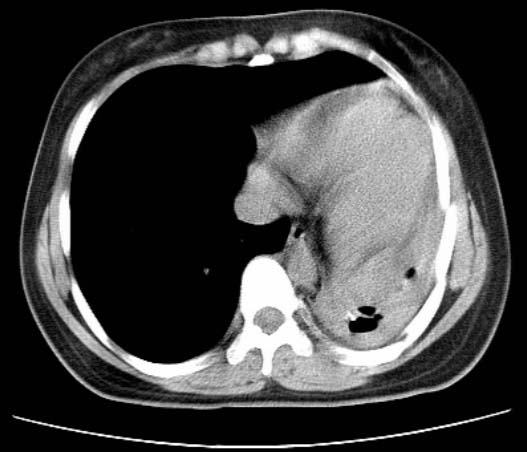

标题: CT25648:求教:是肺发育不全还是结核?

女  20岁。一月前咳血,诊“肺结核”抗痨治疗一月后,咳血停止,现复查。病人精神好。前后ct片对比未见明显变化。既往体检“正常”

1)考虑左肺结核并肺不张、支气管扩张。2)纵隔疝。

考虑左肺结核,左肺毁损,纵膈左偏,既往体检正常不可靠,tb一个月也不会这个样子的,有钙化,应该病程较长,冰冻三尺非一日之寒!

考虑左肺结核,左肺毁损,纵膈左偏,既往体检正常不可靠,tb一个月也不会这个样子的,有钙化,应该病程较长,冰冻三尺非一日之寒